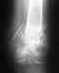

не 24 года. У меня правостороний гемипарез с 9 месяцев. Недавно перенес операцию по методу Ульзибата(по совету врачей). Мне делали правую ногу(2 надреза на Камбалавидной мышце и еще подошвенный апоневроз(кажется он так называется)).После операции заметны коекакие улучшения (стал прямее ходит). Но есть одно обстоятельство , которое меня угнетает. Постояно опухает голеностоп в месте шишек с внутреней и внешней стороны.При ходьбе в ботинках я чувстую дискомфорт и шлепую больной ногой. При выписки рекомендовали сделать платформу на правом ботинке выше на 1 см , т.к. нога короче, но это не слижком помогает.Подскажите пожалуйста что можно предпринять в моей ситуации.